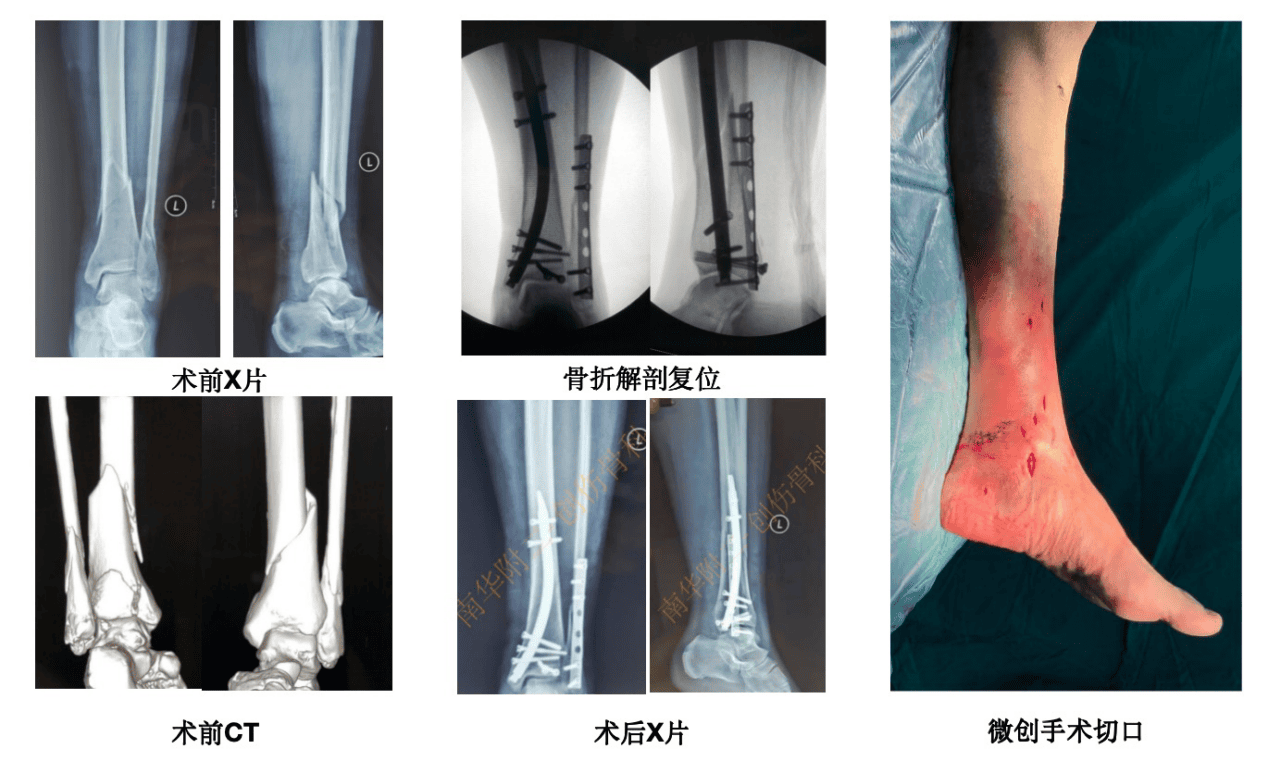

胫骨远端骨折靠近踝关节,复位固定难,局部软组织覆盖和血供差,是临床难题。2014 年 Kuhn 等报道的胫骨远端内侧逆行髓内钉,2020 年引入国内后,我院创伤骨科率先临床应用。该技术优势明显,生物力学稳定性好,简化骨折复位与固定操作,还能避免膝前疼痛等并发症。科室病例数居全国前列,疗效优异,掌握核心技术、临床经验丰富,发表全球最早两篇相关临床报道及 2 篇 SCI 论文。2021 年 2 月,彭斌主任在大博创伤学院推广该技术,目前达国内领先水平,获良好社会反馈。